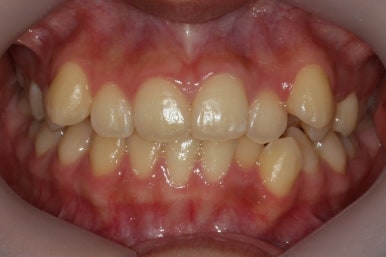

부산교정전문의 키다리아저씨치과에 처음 내원하셨을 때 당시의 입안 모습입니다.

윗니 뿐만 아니라 아랫니 부위에도 덧니가 관찰됩니다. 다른 앞니, 어금니 부위도 약간 삐뚤한 부분이 보입니다.